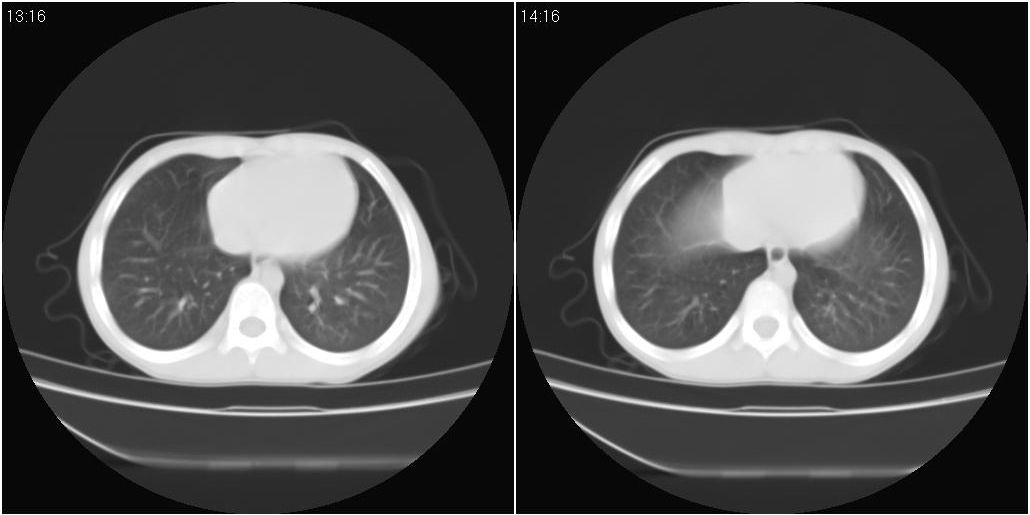

9月8号平片检查情况:

9月15号平片检查情况: